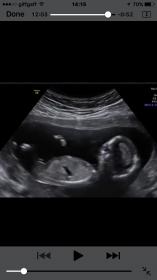

she would love to have your guesses!! She was 13.5 weeks at the scan.

I have gone through her whole video! I can only get these.... any insight at all? XX

I'm going boy from looking at that video; I've screenshot 3 clips that show an angled nub and stacking x

There is a nice boy potty shot at 3:43 and some nice stacking at 5:55 :)